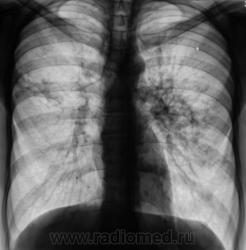

Пациент направлен на рентгенографию органов грудной полости с диагнозом - "Бронхит".

Пациент направлен терапевтом на рентгенографию органов грудной полости с диагнозом - "Бронхит".

Ваше мнение коллеги?

Процесс 2х сторонний, судя по интенсивности "не первой свежести" похоже на туберкулез, хоть не типичная локализация.

Туберкулез, без сомнения. О его форме и стадии без анамнеза судить затруднительно. Возможно, 2-х сторонний инфильтративный в ф. рассасывания, уплотнения, формирования плотных очагов. Ранее "наплевал" себе в язычки.

туберкулез.конечно,есть типичная локализация,однако намерен пробратьсяи туда.где ему совсем не место,что бы нас запутать.

Да, в последнее время, все чаще и чаще, имеются ссылки на наблюдения, свидетельствующие о не типичной (верхушечной, в верхних отделах) локализации туберкулёза.

Разве в представленном случае нетипичная локализация ТБС? Аксиальный субсегмент, SII,SVI? Типичные бронхогенные отсевы в язычки?

"Шестерка", конечно, типичная локализация, подмышечный субсегмент, конечно тоже, но вот "верхушки"?

Есть же статистика по частоте поражения туберкулезом того или иного сегмента. Верхушки поражаются чаще, но не в 100%. Где тонко, там и рвется (focus minoris resistentae).

Меня не покидают сомнения, что "это" - не туберкулёз?